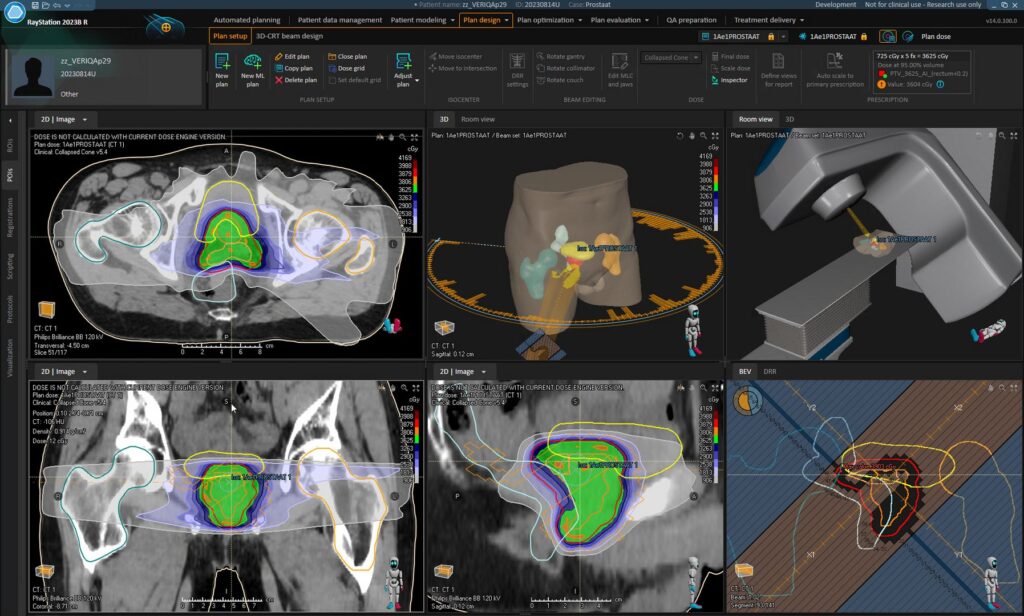

Patiënten met prostaatkanker worden vaak bestraald om de tumor te behandelen. Om te voorkomen dat de omliggende gezonde organen, bijvoorbeeld de blaas, ook straling krijgen, wordt op de computer met speciale software een bestralingsplan gemaakt. Voordat het bestralingsplan kan worden gemaakt, geven de radiotherapeutisch laboranten eerst handmatig aan welke organen er zichtbaar zijn op de CT-scan van de patiënt. Een routinematige steeds terugkerende handeling. En laat AI nu juist voor dit onderdeel geknipt zijn.

AI heeft geen ogen. Hoe kan AI dan de organen herkennen op een CT-scan? Klinisch fysicus radiotherapie, Jean-Paul Kleijnen: “AI is als het ware getraind in het herkennen van organen en botstructuren op een CT-scan. Deze ‘kunstmatige intelligentie’ is nu gekoppeld aan onze software waarmee we onze bestralingsplannen maken. Doel van het bestralingsplan is dat de tumor de juiste hoge stralingsdosis ontvangt en de omliggende organen zo min mogelijk om schade aan gezond weefsel te voorkomen.”